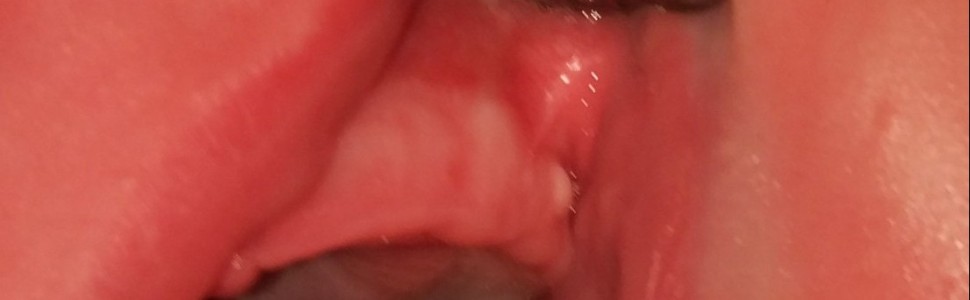

Torbiele listewki zębowej stanowią łagodne zmiany na błonie śluzowej u niemowląt. Przypadek kliniczny 5‑miesięcznego chłopca przedstawia guzek Bohna, obserwowany na wale dziąsłowym szczęki po stronie lewej. Z powodu jego niezapalnego charakteru żadne leczenie nie było wskazane.

Dental lamina cysts are benign oral mucosal lesions in infants. A case report of a five‑month boy presents Bohn’s nodule, observed on the left maxillary dental ridge. Because of its non‑inflamed character any treatment was not indicated.